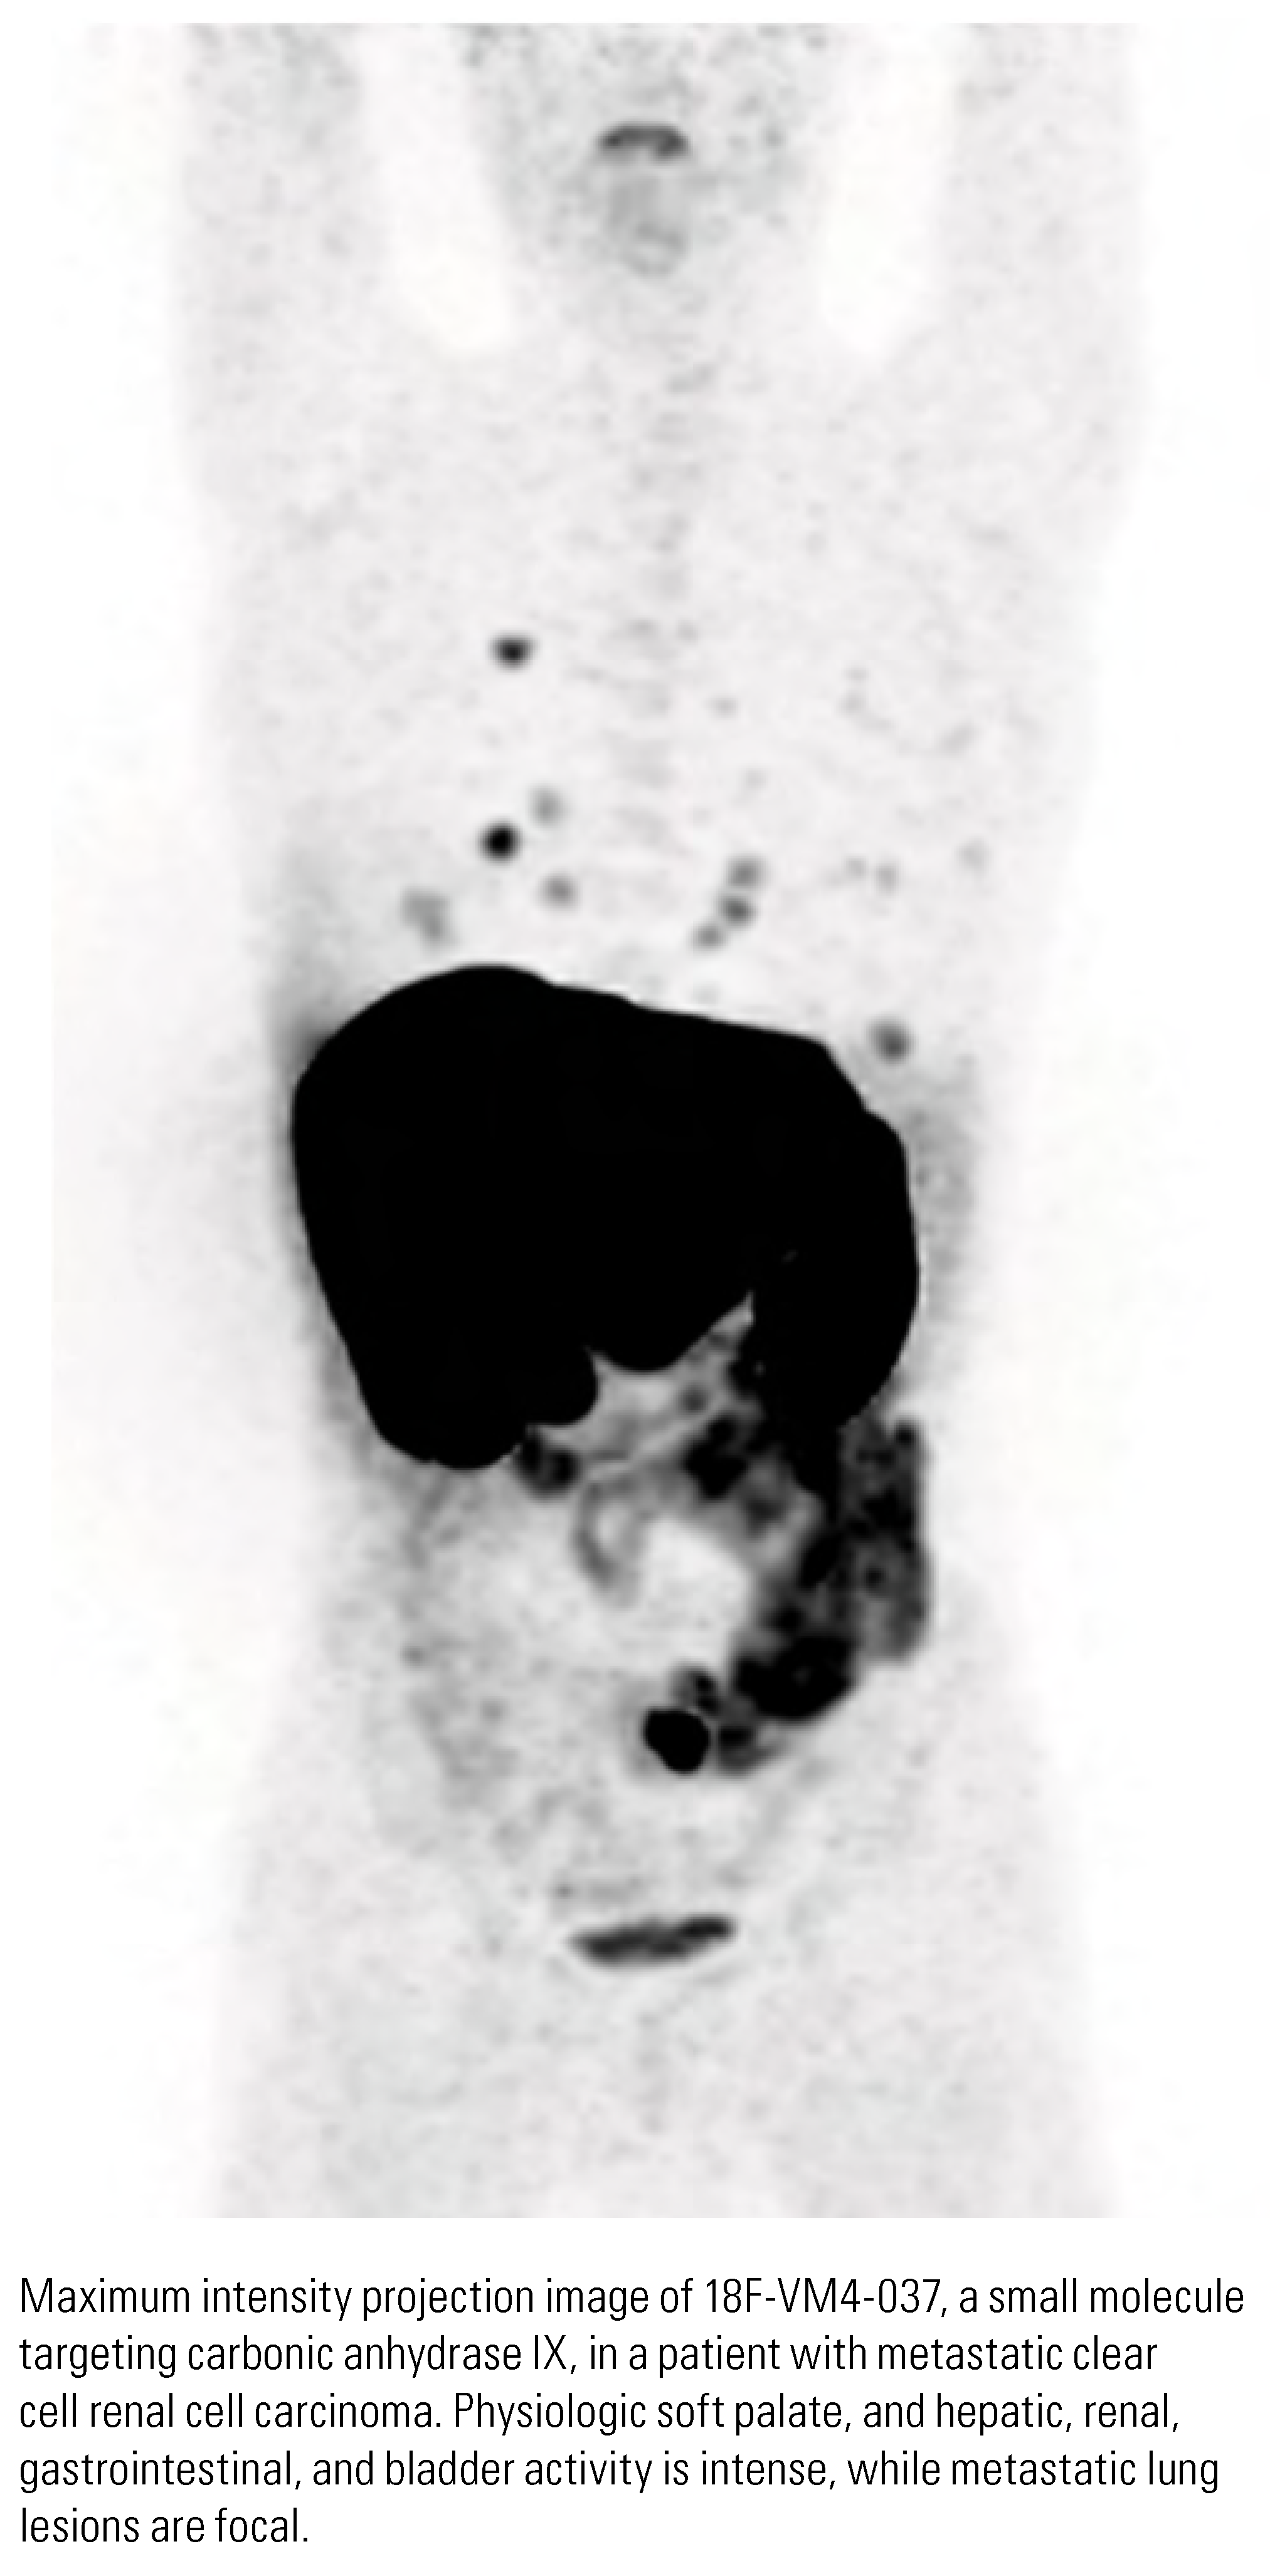

Future Directions